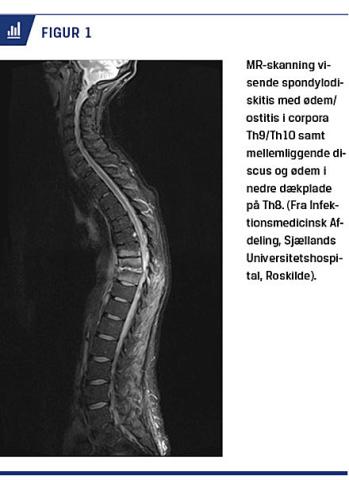

MR-skanning betragtes som billeddiagnostisk guldstandard til udredning af SD [3, 6]. Ved MR-skanning kan man allerede tidligt i forløbet påvise knoglemarvsødem og siden knogleforandringer, og skanningen er fremragende til beskrivelse af anatomisk udbredelse af infektion og abscesser [3, 14]. Sensitivitet og specificitet er begge over 90% [7, 14]. Der skal foreligge T1-, T2- og STIR-sekvens, og der bør altid gives intravenøst kontraststof [3] (Figur 1).